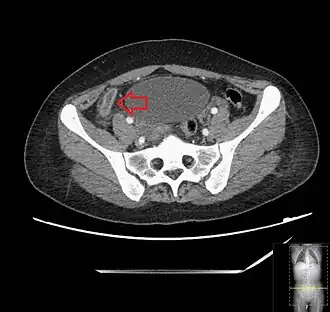

CT scan showing acute appendicitis

A CT scan demonstrating acute appendicitis (note the appendix has a diameter of 17.1 mm and there is surrounding fat stranding).

Where it is readily available, computed tomography (CT) has become frequently used, especially in people whose diagnosis is not obvious on history and physical examination. Although some concerns about interpretation are identified, a 2019 Cochrane review found that the sensitivity and specificity of CT for the diagnosis of acute appendicitis in adults was high.[63] Concerns about radiation tend to limit use of CT in pregnant women and in children, especially with the increasingly widespread usage of MRI.[64][65]

The accurate diagnosis of appendicitis is multi-tiered, with the size of the appendix having the strongest positive predictive value, while indirect features can either increase or decrease sensitivity and specificity. A size of over 6 mm is both 95% sensitive and specific for appendicitis.[66]

However, because the appendix can be filled with fecal material, causing intraluminal distention, this criterion has shown limited utility in more recent meta-analyses.[67] This is as opposed to ultrasound, in which the wall of the appendix can be more easily distinguished from intraluminal feces. In such scenarios, ancillary features such as increased wall enhancement as compared to adjacent bowel and inflammation of the surrounding fat, or fat stranding, can be supportive of the diagnosis. However, their absence does not preclude it. In severe cases with perforation, an adjacent phlegmon or abscess can be seen. Dense fluid layering in the pelvis can also result, related to either pus or enteric spillage. When patients are thin or younger, the relative absence of fat can make the appendix and surrounding fat stranding difficult to see.[67]